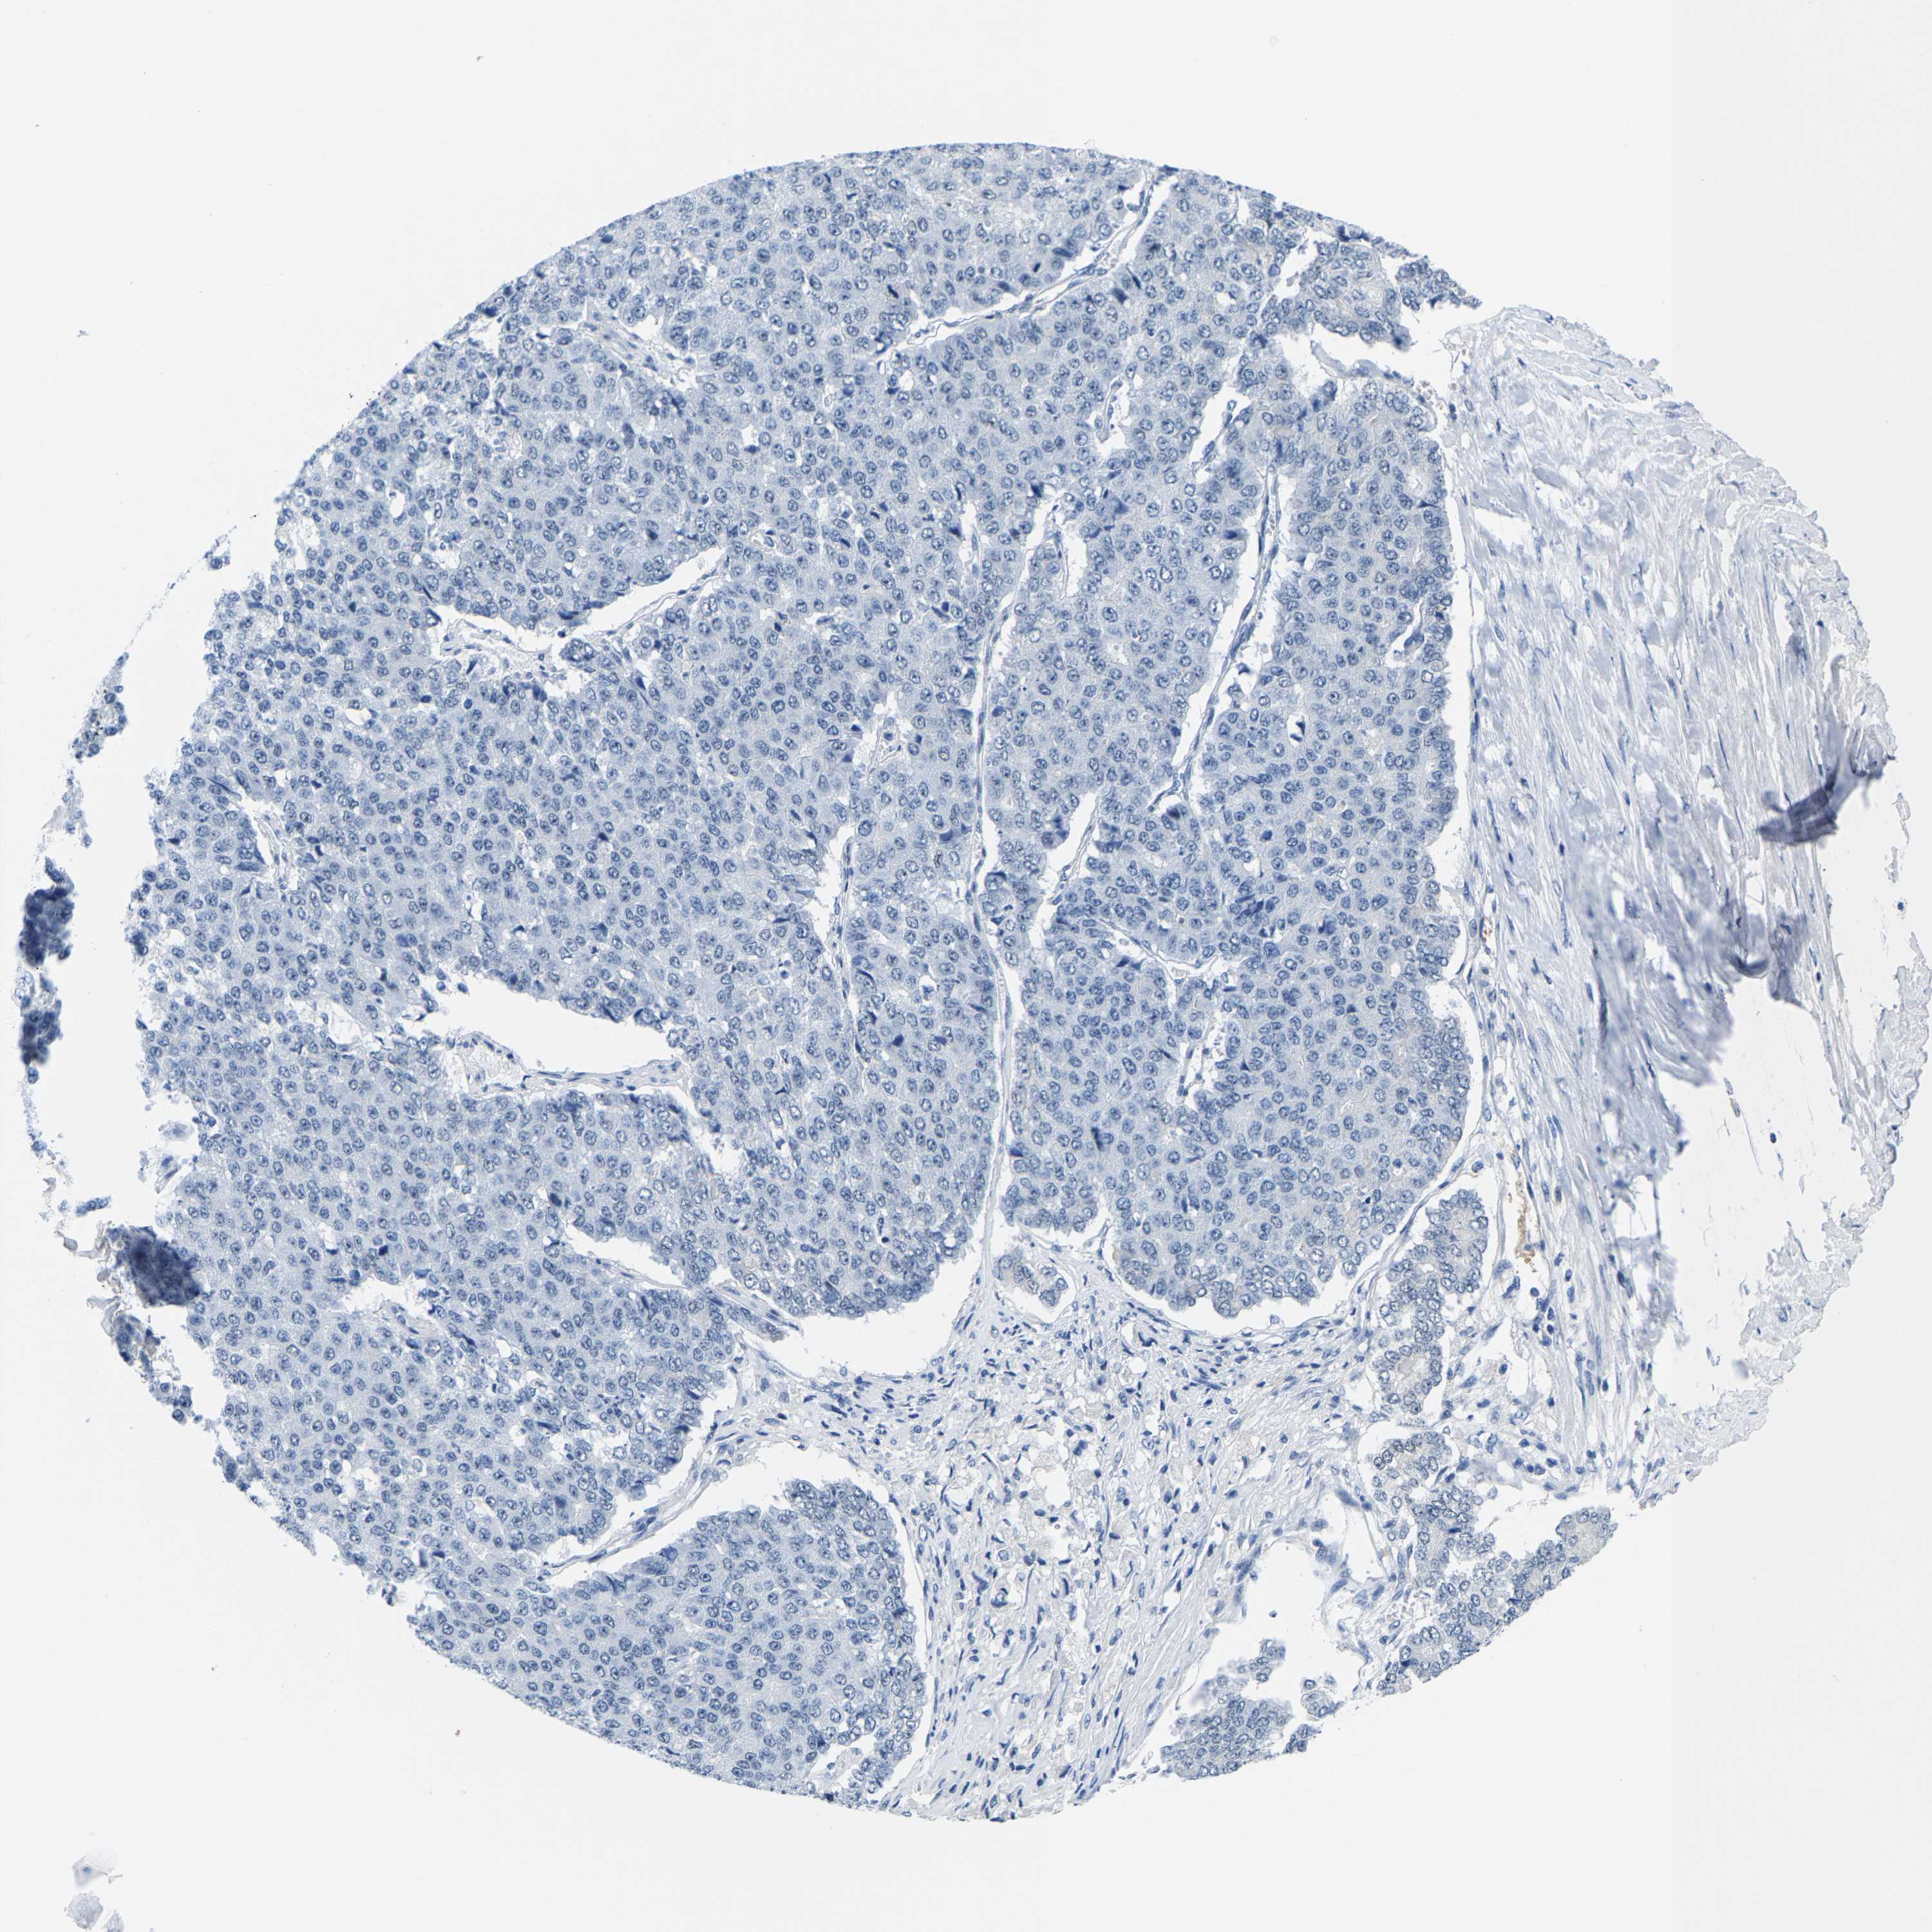

PANCREATIC CANCER - Protein expressioni

A mouse-over function shows sample information and annotation data. Click on an image to view it in a full screen mode. Samples can be filtered based on level of antibody staining by selecting one or several of the following categories: high, medium, low and not detected. The assay and annotation is described here.

Note that samples used for immunohistochemistry by the Human Protein Atlas do not correspond to samples in the TCGA dataset.

Antibody stainingi

Antibody staining in the annotated cell types in the current human tissue is reported as not detected, low, medium, or high, based on conventional immunohistochemistry profiling in selected tissues. This score is based on the combination of the staining intensity and fraction of stained cells.

Each image is clickable and will lead to virtual microscopy that enables deeper exploration of all samples and also displays staining intensity scores, fraction scores and subcellular localization as well as patient and tissue information for each sample.

Antibody HPA019949

Antibody HPA019957

Staining

High

Medium

Low

Not detected

Intensity

Strong

Moderate

Weak

Negative

Quantity

>75%

75%-25%

<25%

None

Location

Nuclear

Cytoplasmic/membranous

Cytoplasmic/membranous,nuclear

Adenocarcinoma, NOS